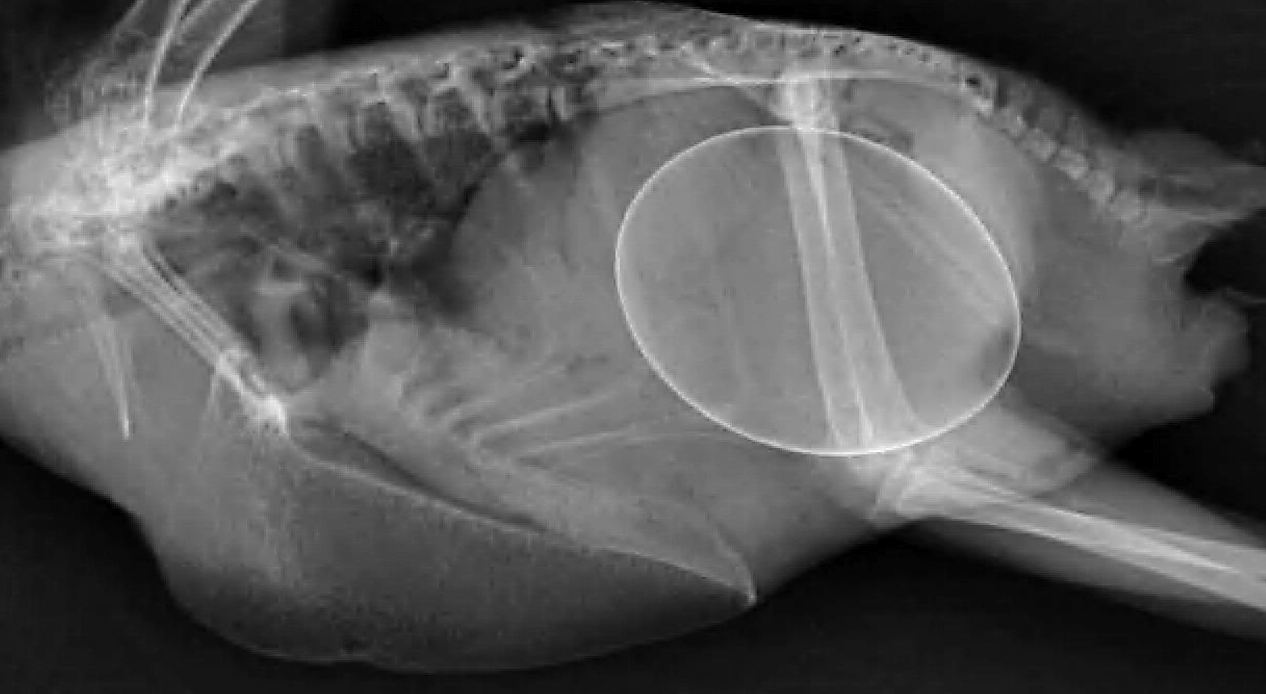

Normal avian wing xray

What are the standard radiographic views for avian wings?

VD (ventrodorsal) and caudo-cranial views.